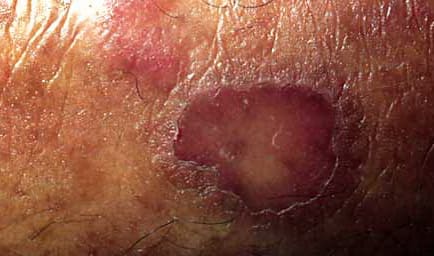

Classic porokeratosis of Mibelli begins during infancy or childhood as asymptomatic small brown to skin-colored annular papules with a characteristic annular border . The well-demarcated hyperkeratotic border is usually more than 1 mm in height, with a characteristic longitudinal furrow. The center of the lesion may be hyperpigmented, hypopigmented, depressed, atrophic, or anhidrotic. Lesions range in diameter from millimeters to several centimeters, but giant lesions measuring up to 20 cm may occur. Such giant porokeratoses are rare and occur predominantly on the lower leg and foot. Large lesions are associated with a higher malignant potential. Multiple lesions may arise; however, they are usually regionally localized and unilateral. The condition may be familial and inherited as an autosomal dominant trait. Lesions persist indefinitely.